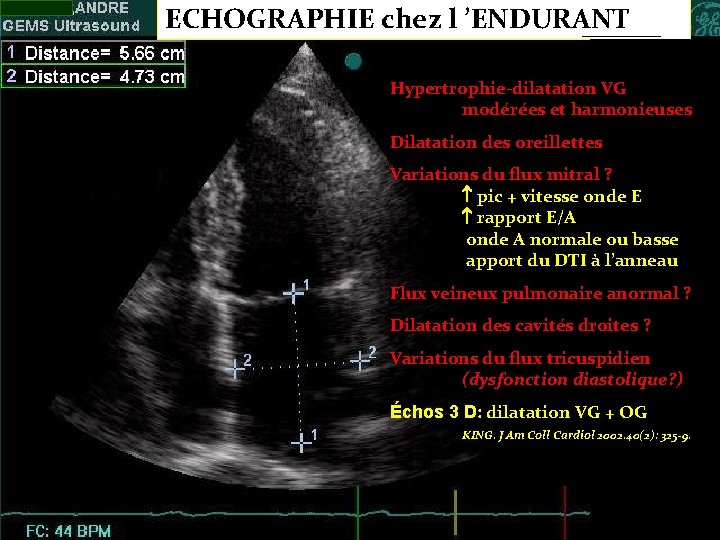

ECHOGRAPHIE chez l ’ENDURANT Hypertrophie-dilatation VG modérées et harmonieuses Dilatation des oreillettes Variations du flux mitral ? pic + vitesse onde E rapport E/A onde A normale ou basse apport du DTI à l’anneau Flux veineux pulmonaire anormal ? Dilatation des cavités droites ? Variations du flux tricuspidien (dysfonction diastolique? ) Échos 3 D: dilatation VG + OG KING. J Am Coll Cardiol 2002. 40(2): 325 -9. CNCF Strasbourg 18 09 03